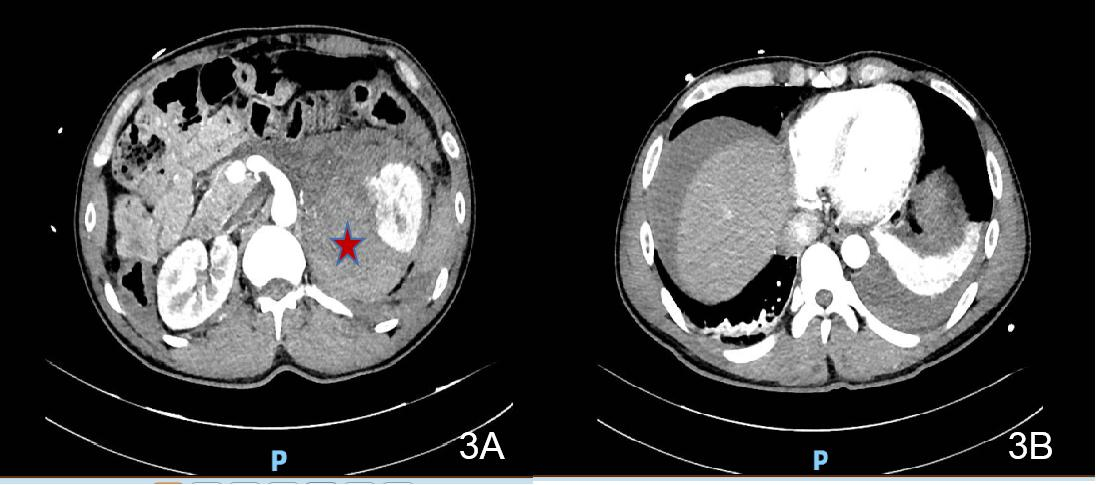

患者1初步诊断考虑急性暴发型病毒性心肌炎与儿茶酚胺心肌病鉴别,患者入院后心率快,呼吸促,满头大汗,面色苍白,双肺湿啰音,出现急性心力衰竭、肺水肿表现,病情进展迅速,随时可能出现心源性休克、恶性心律失常甚至心脏骤停等不良事件,当天转入重症医学科进一步诊治。转入后予以氧疗、控制心室率、营养心肌、抗感染、抗病毒、抗炎、护胃抑酸等支持治疗,效果欠佳,有ECMO辅助指征。征得患者及家属同意,于2017-10-01凌晨行清醒状态局麻下VA-ECMO治疗,使用右侧股动静脉切开置管。使用VA-ECMO模式,初始转速3 000 r/min,血流量3.0 L/min左右,气流量3.0 L/min,氧浓度100%,患者气促逐步缓解,心率90次/min,血压115/82 mmHg,SPO2 100%,尿量约100 mL/h。术前肝素首剂为50 mg,术后维持量为4~6 mg/h,APTT 43.8~70.3 s,ACT 130~168 s,全身各部位无明显出血,膜肺无血栓形成,在ECMO支持期间,同时予抗感染、抗病毒(阿昔洛韦)、人免疫球蛋白、艾司洛尔控制心室率(后过渡至酒石酸美托洛尔片)、控制血压等治疗。2017-10-02心脏彩超示EF下降至16%,2017-10-04将EF恢复至48%,撤离VA-ECMO。2017-10-06心脏彩超:左室心尖运动稍减弱,主动脉瓣返流(轻),二、三尖瓣返流(轻),左室射血分数57%,舒张功能稍减退。2017-10-10行冠脉造影未见明显异常。患者病情好转出院。2017-11-20返院复诊,查腹部CT发现右侧肾上腺区肿块,考虑嗜铬细胞瘤(见图 1),予服用“酚苄明”血压控制良好。2017-12-14复查心脏彩超提示:二、三尖瓣返流(轻度),左室收缩、舒张功能正常,EF 70%,肺动脉压正常(25 mmHg)。2017-12-15行择期手术治疗,病理结果符合嗜铬细胞瘤,术后患者血压恢复正常。患者最后诊断“嗜铬细胞瘤、儿茶酚胺心肌病”。

| 图 1 2017-11-20患者1腹部CT(右侧肾上腺区肿块) |